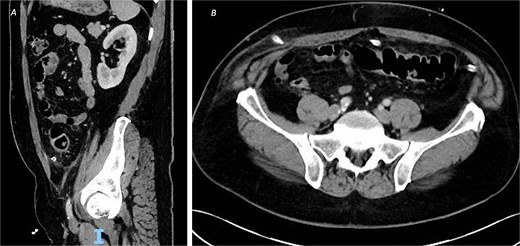

An urgent contrast-enhanced computed tomography (CT) abdomen–pelvis was performed, which revealed a 3.7-cm linear hyperdense foreign body, consistent with a fish or chicken bone, penetrating the wall of the sigmoid colon with associated surrounding pericolic fat stranding and small amount of localized pericolic air denoting small perforation (Fig. 1); there was no evidence of abscess formation, or distant free air.

CT of the abdomen and pelvic with contrast, demonstrating an ingested foreign body with localized perforation and pericolic inflammatory changes, in both (A) sagittal view and (B) axial view.